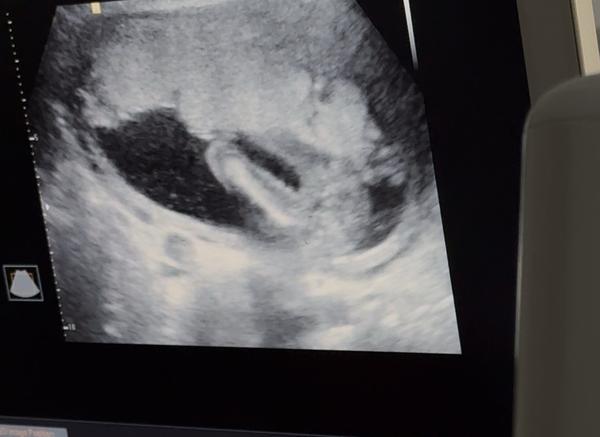

My se snažili o miminko 3 roky, dvakrát IUI a 1x IVF se 3 vklady a za tu dlouhou dobu jen jednou biochemické. Teď se jako zázrakem zadarilo po laznich přirozeně a jsem 6tt + 5 cca. Nicméně k minulým zkušenostem mám obavy a ráda bych si s někým psala a uklidnila se, jelikož ve svém okolí nemám nikoho, kdo by na tom byl teď podobně jako já a kromě manžela to nemám moc s kým sdílet.

@puraniani my jsme se snazili 6 let.. pred dvema lety jedno biochemicke 🙏 premlouvala jsem pritele porad na ivf jednou jsme tam uz i sedeli ale on to hrozne nechtel casto jsme se kvuli toho dohadovali.. rikala jsem si ze uz dite nebude.. ted jsme jeli koncem srpna na dovcu a prijela jsem 2 v 1 😻🩷 byla jsem na kontrole 5+6 trosku jsem si tu kontrolu vynutila 😁 a uz bylo videt i srdicko ted jsem 6+2 a doufam ze vse bude v poradku 🩷 strach je porad ale rikam si ze co se ma stat se stane a nebudu myslet na spatne veci nekdy to nejde ale stejne nic neovlinim 🍀 takze drzim pesti vsem 😻